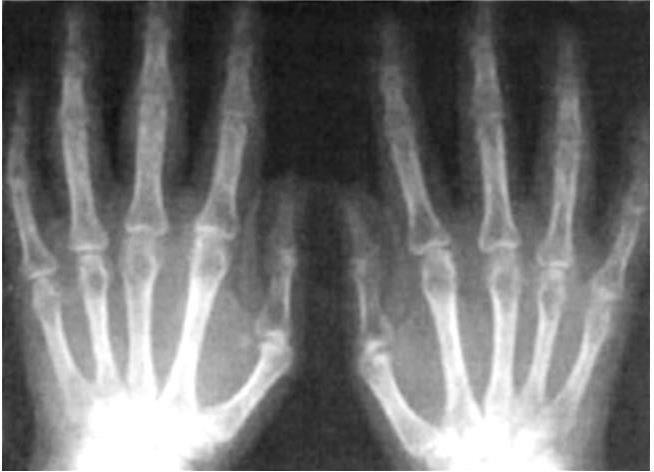

Рентген: Как выглядит здоровая пястная кость

Раздел: Картинки на заметку